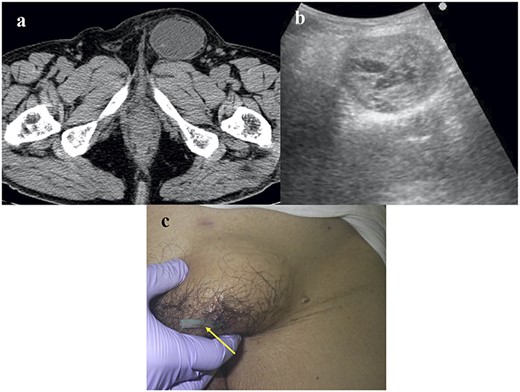

An anterior rather than a laparoscopic approach was selected. The cyst was separated from the spermatic cord (Fig. 2a) and its connecting vessels were divided (Fig. 2b). A prophylactic onlay mesh was placed to reinforce the posterior wall of the inguinal canal, despite the absence of hernia recurrence.

Intraoperative and pathological findings. (a) The CEH (arrow) was separated from the spermatic sheath (arrowhead). (b) The vessels (arrow) connected to the CEH were divided. (c) Cut surface of the resected specimen. (d). Hematoxylin–eosin staining of the CEH (×100). The specimen contained inflammatory cells (arrow), such as lymphocytes and macrophages, and the hematoma (dotted line) was capsulized with collagen fibers (arrowhead).

The cut surface of the resected specimen contained the fascia, and the content had a mosaic-like appearance (Fig. 2c). Pathologically, the cyst consisted of an old hematoma, chronic inflammatory infiltrates, such as lymphocytes and macrophages and fibrous tissue (Fig. 2d). The final diagnosis was CEH. The postoperative course was uneventful, and no recurrence of CEH or inguinal hernia was observed. The treatment strategy is presented in Fig. 3.